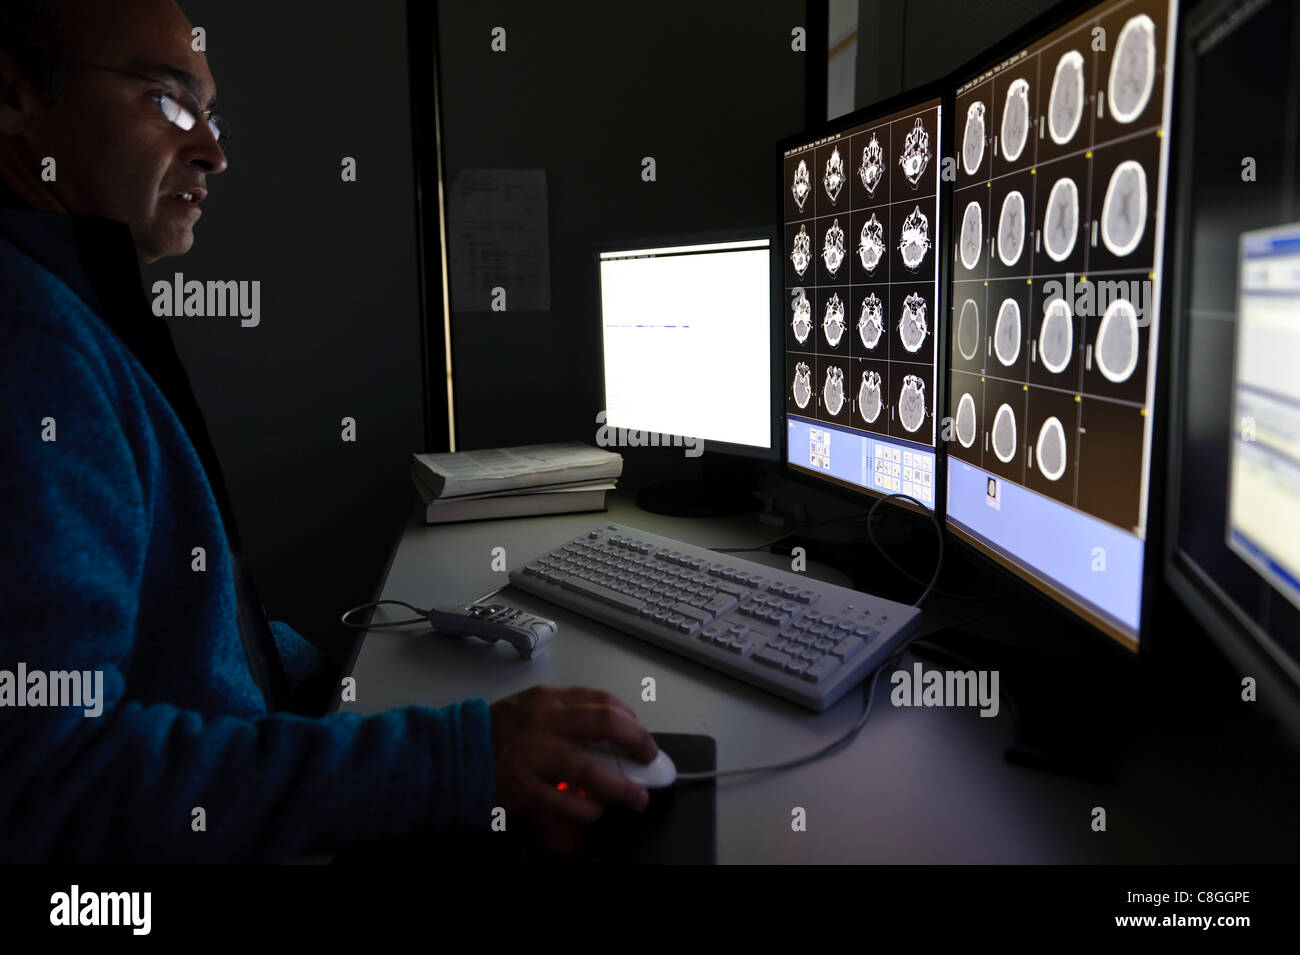

Doctor examining CT scan cérébral sur les écrans d'ordinateur Banque D'Imageshttps://www.alamyimages.fr/image-license-details/?v=1https://www.alamyimages.fr/photo-image-doctor-examining-ct-scan-cerebral-sur-les-ecrans-d-ordinateur-39702390.html

Doctor examining CT scan cérébral sur les écrans d'ordinateur Banque D'Imageshttps://www.alamyimages.fr/image-license-details/?v=1https://www.alamyimages.fr/photo-image-doctor-examining-ct-scan-cerebral-sur-les-ecrans-d-ordinateur-39702390.htmlRMC8GGPE–Doctor examining CT scan cérébral sur les écrans d'ordinateur

CT scan cérébral sur les écrans d'ordinateur Banque D'Imageshttps://www.alamyimages.fr/image-license-details/?v=1https://www.alamyimages.fr/photo-image-ct-scan-cerebral-sur-les-ecrans-d-ordinateur-39702393.html

CT scan cérébral sur les écrans d'ordinateur Banque D'Imageshttps://www.alamyimages.fr/image-license-details/?v=1https://www.alamyimages.fr/photo-image-ct-scan-cerebral-sur-les-ecrans-d-ordinateur-39702393.htmlRMC8GGPH–CT scan cérébral sur les écrans d'ordinateur

Doctor examining CT scan du cerveau à l'ordinateur Banque D'Imageshttps://www.alamyimages.fr/image-license-details/?v=1https://www.alamyimages.fr/photo-image-doctor-examining-ct-scan-du-cerveau-a-l-ordinateur-39702411.html

Doctor examining CT scan du cerveau à l'ordinateur Banque D'Imageshttps://www.alamyimages.fr/image-license-details/?v=1https://www.alamyimages.fr/photo-image-doctor-examining-ct-scan-du-cerveau-a-l-ordinateur-39702411.htmlRMC8GGR7–Doctor examining CT scan du cerveau à l'ordinateur